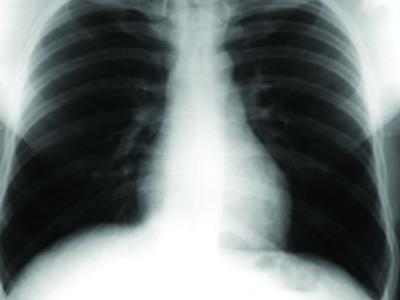

Longitudinal study of nasopharyngeal microbiota in Indigenous children with bronchietasis while receiving long-term azithromycin or placebo treatment

This project is an extension of the Bronchiectasis Intervention Study (BIS). The project extends the original study by adding microbiota analysis. This is a longitudinal study of microbiota present in...

Exploring the PBB microbiome: Do airway bacterial community structures correlate with inflammatory measures?

Our initial study, funded by the Channel 7 Children’s Research Foundation, investigated the microbiota associated with the upper and lower respiratory tract in 35 children with chronic suppurative lung disease,...

LOTUS - Long term follow up improves clinical care and respiratory outcomes for Indigenous children.

The LOTUS study is an extension of previous bronchiolitis and chronic suppurative lung disease (CSLD) (includes non-cystic fibrosis bronchiectasis) studies. This research project is being conducted over three year and...